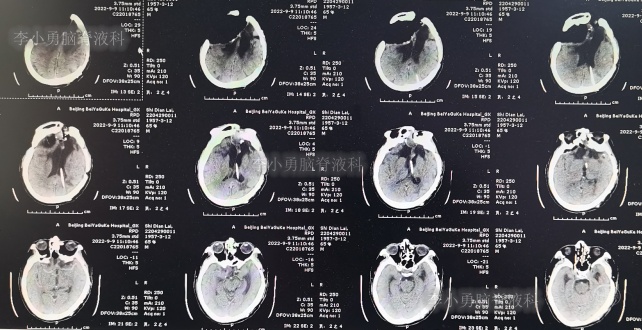

继续治疗1个半月,期间4次(2013年2月15日、2013年2月27日、2013年3月5日、2013年3月11日)查头颅CT(图-19、图-20、图-21、图-22)均示脑室在不断的变好。

图-19:2013年2月15日头颅CT

图-20:2013年2月27日头颅CT

图-21:2013年3月5日头颅CT

图-22:2013年3月11日头颅CT

2013年3月12日(入院治疗132天),拔除了头部外引流管(图-23)。

图-23:2013年3月12日头颅CT

2013年3月15日(入院治疗135天),查头颅CT示脑室周水肿减轻(图-24)。

图-24:2013年3月15日头颅CT

出院后1年即2014年7月31日,自己行走正常,但上下楼需扶着,言语少,日常生活基本自理(图-29),查头颅CT示颅骨缺损(图-30)。

图-30:2014年7月31日头颅CT